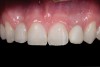

Fig 1. Initial presentation. Note midline shift to right, missing right lateral incisor, and diminutive left lateral incisor in crossbite.

Figure 1